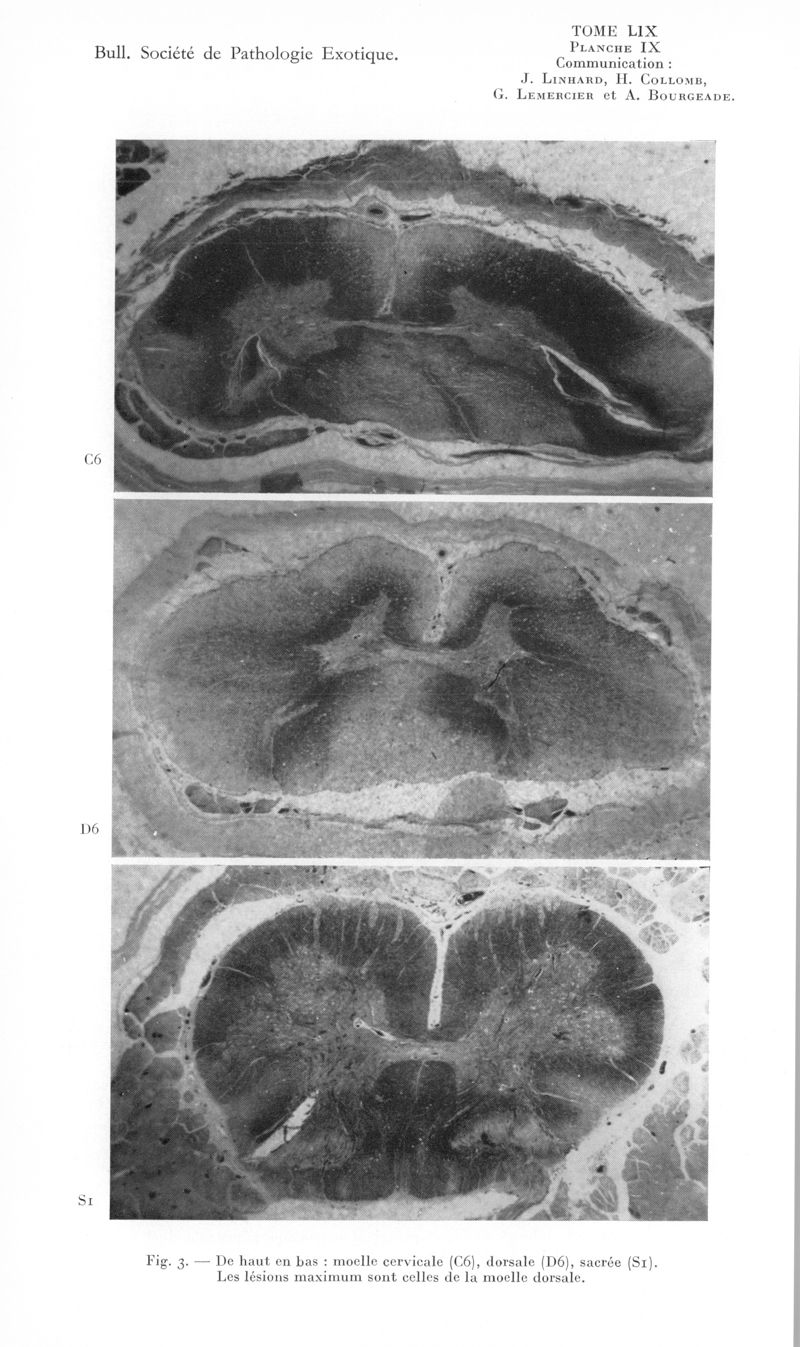

Bulletin de la Société de pathologie exotique et de ses filiales

1966, tome 59. - Paris : Masson, 1966.